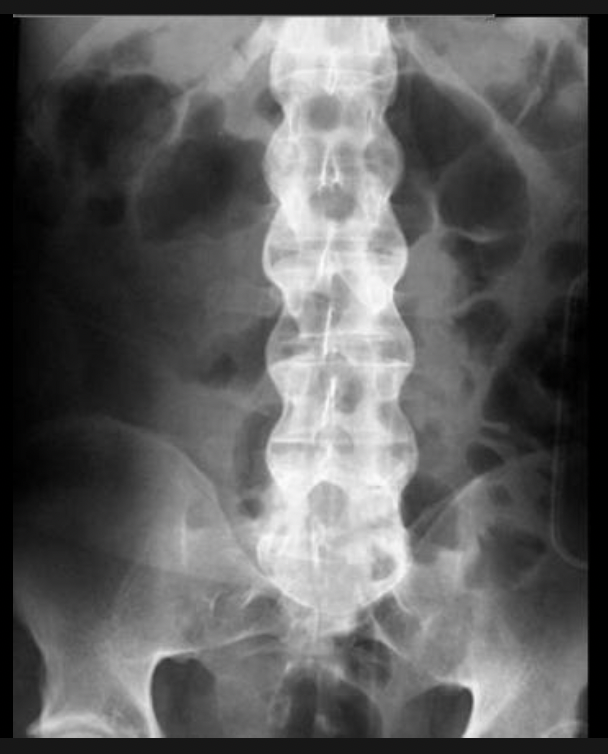

Ankylosing spondylitis